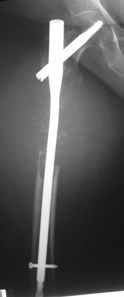

Саркомные переломы обычно не срастаются, по этому не зависимо от места метастаза фиксатор устанавливается максимально длинный и обязательно с блокировкой что бы сохранять длину кости даже после роста метастаза или при дополнительно метастазировании. В Вашем случае блокировочные гвозди выглядят тонкими и проведены только через один кортекс. Гвоздь толщиной более 10 мм с блокировочными шурупами 4-5 мм проведенные через обе кортикальные пластинки может обеспечить опороспособность даже если перелом не срастется или литический процесс распространится.

Посылаю первый снимок, который попался по руку.